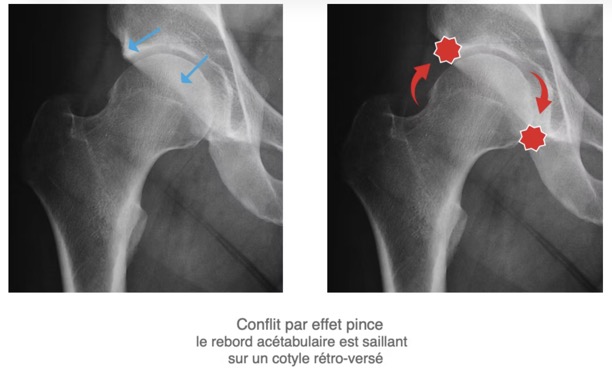

- 2. Le conflit de type PINCER (b) : bord de l'acétabulum trop proéminent ou cotyle trop profond